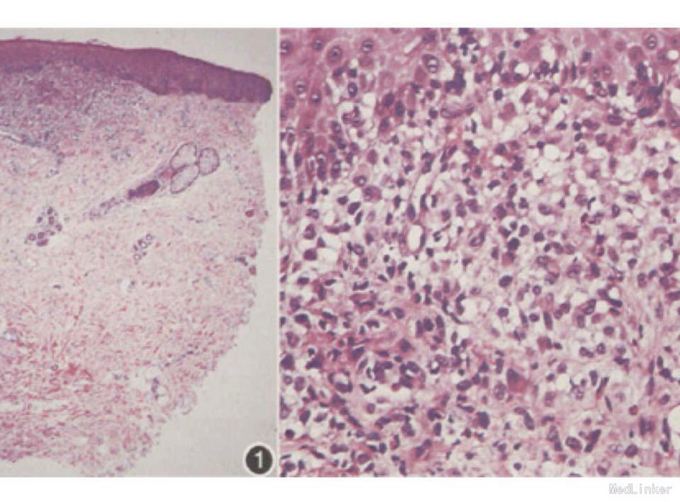

查体:外阴可见数个米粒大小红丘疹,无压痛。 辅查:病理组织示局部真皮浅层片状增生的组织细胞,并向上侵犯表皮。部分核呈肾形。免疫组化Cd 1a,CD68,S-100均阳性。全身Ct未见转移灶。

诊断:原发性外阴朗格汉斯细胞组织细胞增多症 处理:明确无其他器官累及,暂未行化疗,嘱其出院随访。